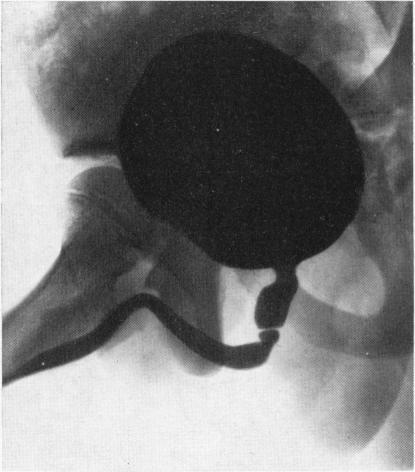

FISHER O D, FORSYTHE W I

Arch Dis Child. 1954 Oct;29(147):460-71. doi: 10.1136/adc.29.147.460.